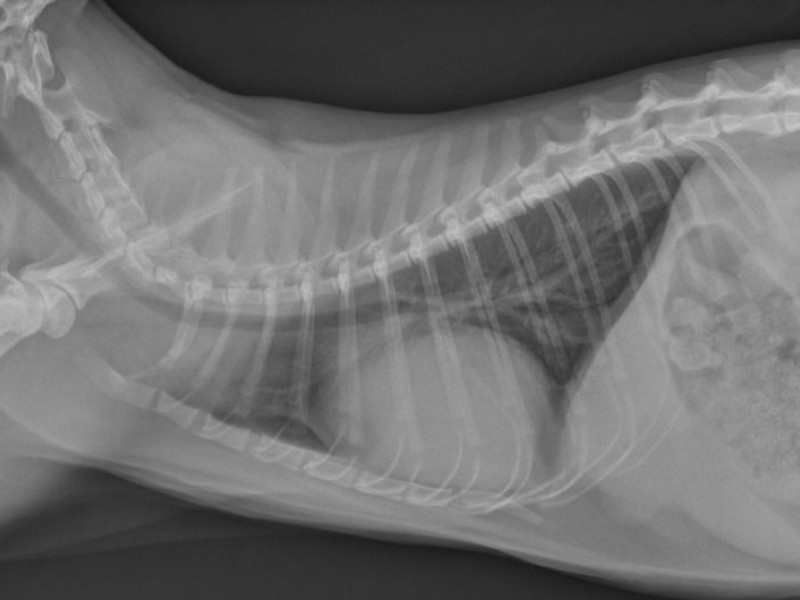

There is a severe globoid enlargement of the cardiac silhouette (more than 2,5 IC spaces), a mild distention of the caudal vena cava (wider than 1,5 times the aorta).

The liver is increased in size, extending caudally to the rib cage and shows rounded edges.

Normal appearing lungs, no congestion of the pulmonary vasculature.

Différential diagnostic:

- Péricardial effusion compatible with the globoid cardiomegaly and the caudal vean cava and liver congestion

- Dilated cardiomyopathy: rarely diagnosed in cats nowadays. It was linked to a deficiency in taurine but the food is now complemented.

- Burn out hypertrophic or restrictive cardiomyopathy but no signs of pulmonary congestion are detected, so this is less likely.

Complementary exam:

Echocardiography, with aspiration of the liquid.

The main causes of pericardial effusion in cats are right heart failure, FIP and lymphoma. In this immunossupressed cat both FIP and lymphoma are possible differentials.